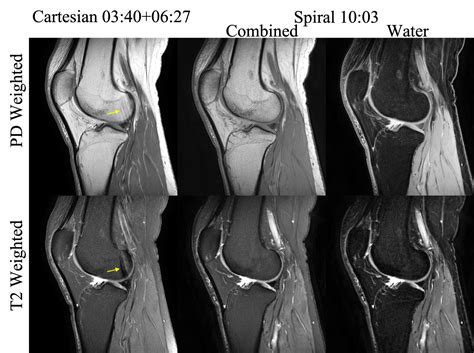

Understand your health with our expert guide to interpreting Knee MRI images. We break down common scan findings, including meniscus tears, ligament injuries, and cartilage damage. Learn what your radiology report means, how diagnostic imaging aids treatment planning, and what to expect during your orthopedic scan to ensure better recovery outcomes for your joint health.